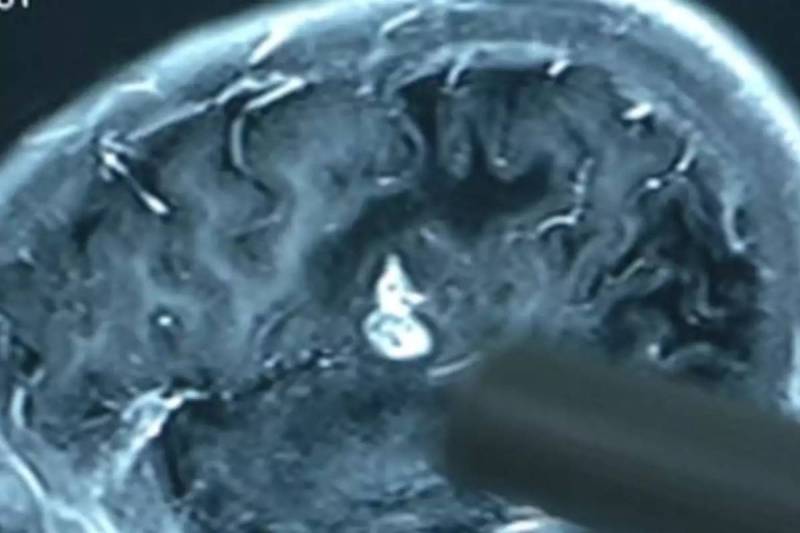

संयुक्त राष्ट्र अमेरिका (USA) में एक अजीब केस सामने आया है। यहां एक शख्स को लगभग 4 महीने से सिरदर्द की शिकायत थी। पहले डॉक्टर्स से इलाज कराया तो उन्होंने इसे माइग्रेन (Migraine) बताया लेकिन जब इस शख्स को असहनीय दर्द होने लगा और अस्पताल गया तो वहां डॉक्टर्स ने उसके दिमाग की जांच की तो हैरानी वाला नज़ारा देखने को मिला। न्यूयॉर्क पोस्ट की खबर के मुताबिक 52 साल के इस पीड़ित के मस्तिष्क का जब सीटी स्कैन किया गया तो उसके दिमाग के दोनों किनारों पर पहले तो सिस्ट जैसी चीज दिखाई दी और जब इस सिस्ट की जांच हुई तो ये सिस्ट नहीं बल्कि टेपवर्म (Tapeworm) यानी फीते जैसे कीड़े के अंडे निकले और जिंदा कीड़ा भी निकला।

जिन डॉक्टर्स ने इस शख्स की जांच की तो पता चला कि इस शख्स को परजीवी संक्रमण न्यूरोसिस्टीसर्कोसिस (Neurocysticercosis) है। जो अधी पकी हुई बेकन (Bacon) (सुअर की पीठ का मांस) खाने से हुआ है। डॉक्टर्स ने इस शख्स को अधपकी बेकन खाने से मना किया था क्योंकि वो बचपन से इसे खा रहा था। इस अधपके बेकन (Bacon) में मौजूद बैक्टीरिया के सूक्ष्म अंडे उसका आंत में प्रवेश कर गए जिससे ये कीड़ा पैदा हो गया। पैदा हो गया जो दिमाग में रहने लगा और रेंगता रहा यही नहीं इन कीड़ों ने दिमाग में ही अंडे देना शुरू कर दिया। वहीं कुछ कीड़े (Tapeworm) शख्स के मल के साथ बाहर निकल गए।